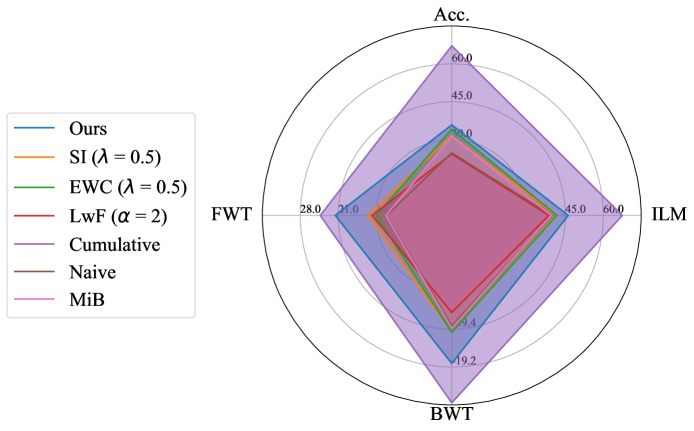

Performance comparison with others: For the considered medical applications, the primary concern will not be on improving zero-shot performance (FWT) but rather on minimizing forgetting (BWT) and enhancing the average DSC of the model (ACC and ILM). While FWT is reported for completeness, our analysis emphasize ACC, ILM, and BWT. Table 2 presents the ACC, ILM, BWT, and FWT values for all methods across sequences S1, S2, S3, and S4. Across all sequences, CL approaches (GDumb, Replay, MiB, LwF, SI, EWC, and the proposed method) mostly outperform naive training, highlighting the importance of mechanisms to mitigate catastrophic forgetting in UNet-based segmentation tasks. Further, as expected, approaches storing past data partially (Replay, GDumb) or fully (cumulative, joint training) show higher performance compared to methods (naive, MiB, LwF, SI, EWC, and the proposed approach) with no access to past exemplars. When comparing the proposed method to other buffer-free approaches (MiB, LwF, SI, EWC), it consistently achieves superior performance in all the sequences S1, S2, S3, and S4. Unlike these existing CL methods, which penalize large deviations from previously learned weights through response-level regularization terms in the training loss, the proposed approach introduces a drift-based dynamic penalization factor along with a latent-level regularization. This drift-based dual distillation allows for more effective mitigation of catastrophic forgetting. The proposed method shows a positive gain in (ACC, ILM, BWT) over best performance achieved among state-of-the art buffer-free approaches (blue colored in Table 2). Specifically, we observe an improvements of (25.51%, 9.23%, 34.34%) in S1, (6.57%, 25.28%, 31.85%) in S2, (4.85%, 11.02%, 40.15%) in S3, and (7.67%, 10.65%, 17.62%) in S4. For intuitive visualization, radar plots for S1, S2, S3, and S4, comparing cumulative, naive, the best-performing buffer-free methods, and the proposed approach are provided in Fig. 6 of Appendix.

Appendix B Radar Plot based Comparison

For intuitive visualization, Fig. 6 provides a radar plot comparing cumulative, naive, the best-performing buffer-free CL methods, and the proposed approach. In all the formulated dataset sequences, the proposed method demonstrates clear superiority over all other approaches except cumulative, which serves as the upper performance bound.